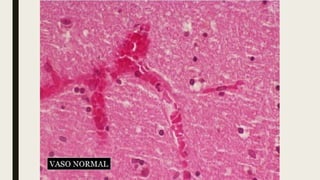

Reações celulares e vasculares da inflamação

aguda. As principais

manifestações locais da inflamação aguda

comparadas ao normal são

(1) dilatação vascular e aumento do fluxo

sanguíneo (causando eritema e

calor), (2) extravasamento e deposição de líquido

e proteínas plasmáticas

(edema) e (3) emigração e acúmulo dos leucócitos

(principalmente neutrófilos)

no local da lesão.